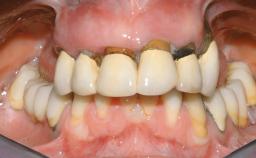

Immediate Loading of Six Implants in the Maxilla and Final Restoration with a Full-Arch CAD/CAM Zirconia FDP

A 63-year-old male patient was referred for a consultation and treatment of partial edentulism in the maxilla. The patient presented with residual anterior teeth and declined a partial removable prosthesis. He reported that the maxillary posterior teeth had been extracted due to mobility and periodontal disease two months before the consultation. The patient’s chief complaint was that his residual maxillary teeth were mobile and that he was unable to chew. The patient’s desire was a stable and comfortable fixed maxillary rehabilitation. The patient was a light smoker (fewer than 10 cigarettes/ day), and his medical history was without significant findings. He was not on any regular medication at the time of consultation. The extraoral examination revealed a normal physiognomy with a correct distribution of the facial thirds. The patient presented a low lip line, and the transition line between teeth and soft tissues was not exposed during a forced smile.